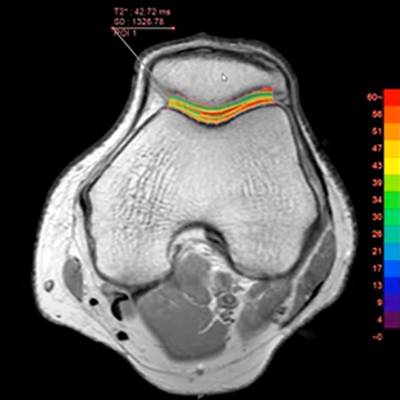

Using MR data with different TE and spin lock times, this protocol measures T2, T2*, or T1rho values of the specified ROI and shows color maps.